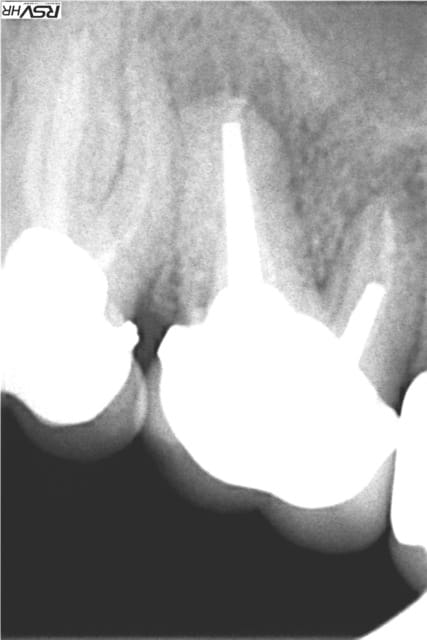

Les délires continuent !(clin d’œil doc Marcus)

37 fêlure-fracture au niveau du plancher en cours de RTE(1er radio avant RTE)

extraction dans la séance forage entre les racines extraction des racines re- forage après dans le septum

pose implant 7 mm long10mm le 11.06.2012

le 25.09.2012 pose d'un faux moignon titane transvissé et

couronne provisoire

RTE en cours sur 36

CCM définitives après

CBCT en 2014 OK pour l'implant